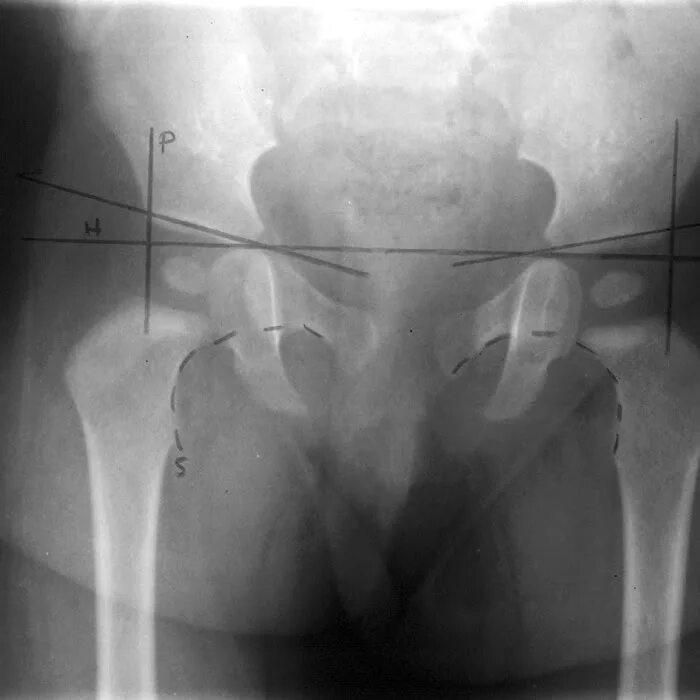

Дисплазия тазобедренных суставов как выглядит